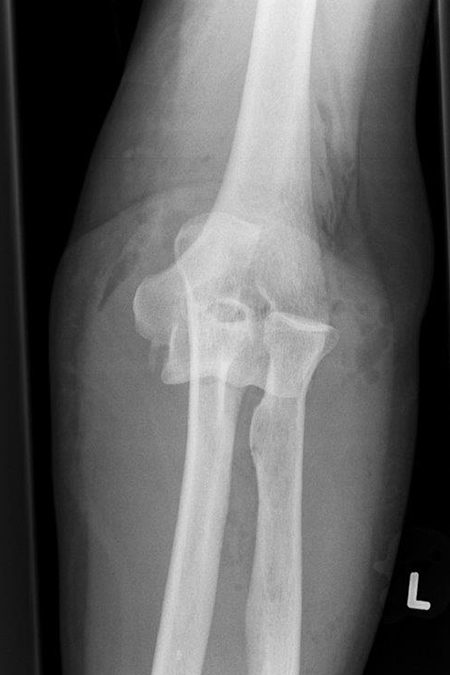

ELLENBOGENINSTABILITÄT

AKUT - UNFALLBEDINGT

Bei einer Verrenkung (Luxation) des Ellenbogengelenkes kann es zu schweren Verletzungen des Knochens und der Weichteile kommen. Typisch ist der Sturz auf den leicht gebeugten außengedrehten Arm der zu einer Verrenkung (Luxation) des Ellenbogengelenks führt. Dabei springt in den meisten Fällen das Speichenköpfchen über die Oberarmrolle hinweg nach hinten heraus und kann sogar an der Oberarmrolle zerbrechen (Typ Mason IV).

Je nach Ausmaß der Verrenkung reichen die Kapsel- und Bandeinrisse um das Gelenk bis zur Ellenseite herum und führen so zu einer Instabilität des Ellenbogengelenks. Die unkomplizierte Luxation, die schnell einer Einrenkung (Reposition) zugeführt wird, heilt in den meisten Fällen auch ohne Operation aus.

Zeigt die Stabilitätsprüfung des Gelenkes nach Reposition eine Instabilität oder liegen Frakturen vor, wird eine operative Rekonstruktion erforderlich.

Die Operation dieser komplizierten Verletzungen zielt darauf ab die verletzten Bandansätze (ulnares und radiales Seitenband, beugeseitige Kapsel) wie auch die knöchernen Verletzungen (Speichenköpfchenbruch – oft zertrümmert, proc. Corornoideus) stabil wieder her zu stellen. Ziel ist es das Ellenbogengelenk frühzeitig stabil zu bewegen, um eine Einsteifung zu verhindern.

Ventrale Luxation Ellenbogen

Ellenbogengelenk herausgesprungen frontal

Ellenbogengelenk herausgesprungen seitlich